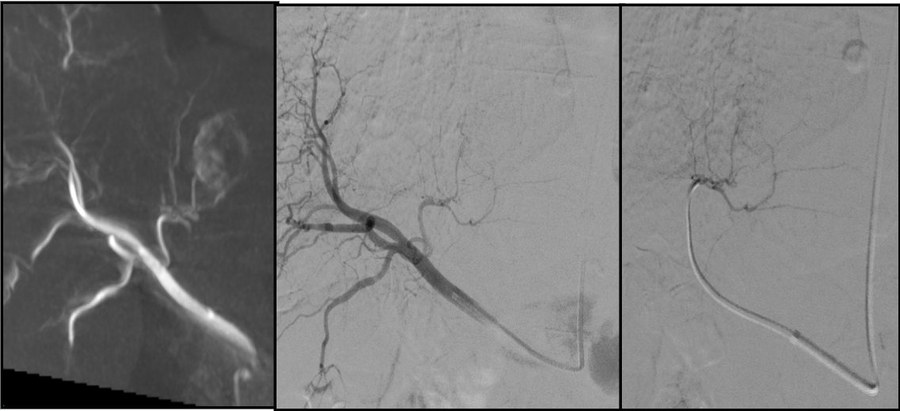

Angioplastie AOMI, artères rénales, recanalisation veineuse, thrombolyse, urgences vasculaires.

Andrologie 💙Troubles de l'érection : fuite veineuse

Embolisation des veines péniennes pathologiques. Alternative à la chirurgie, ambulatoire.